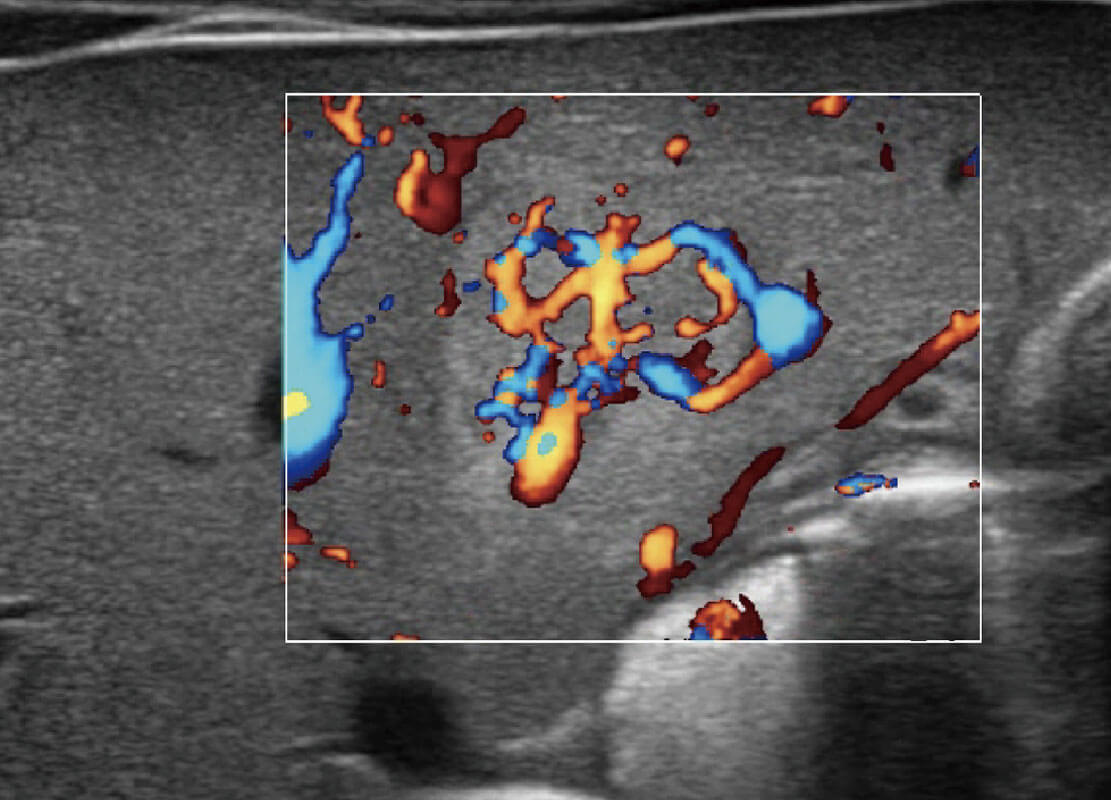

P60搭載一系列胎兒心臟成像技術(shù),實(shí)現(xiàn)精細(xì)的胎兒心臟評(píng)估。

四腔心血流